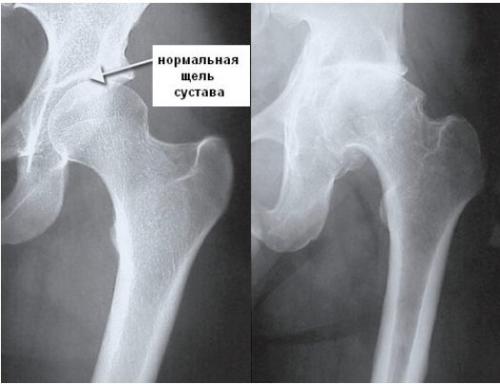

Симптомы появляются только при сильном повреждении хрящевой поверхности. Клинические исследования, а также рентгеновские снимки помогают врачам с точностью поставить диагноз. Сначала — это заболевание хряща. На прогрессирующих стадиях коксартроза повреждаются связки, костные структуры, суставная капсула, синовиальная оболочка и мышцы. В таких случаях медики говорят об остеохондрозе тазобедренного сустава.

- Первая степеньпротекает практически незаметно и бессимптомно. Максимальные проявления – слабая ноющая боль после физических нагрузок, которую часто путают с усталостью. Изменения обнаруживаются только при рентгенологическом исследовании. По краям суставных поверхностей видны небольшие костные разрастания, а под хрящевой тканью кость уплотняется. Это первый тревожный сигнал, но, к сожалению, редко кто начинает лечение на этой стадии.

У вас обнаружили остеоартроз еще на первой стадии? Это большое везение!

- Вторая степеньсопровождается воспалительным процессом, припухлостью, болью при физических нагрузках. Начинаются прогрессирующие деформации сустава, он перестает адекватно функционировать – боль усиливается. Остеофиты ограничивают подвижность, во время движений появляются характерные щелчки. На снимке заметно сужение суставной щели (выраженный остеосклероз) – примерно на треть от нормы.

- Третья степень– крайне тяжелая и по субъективным ощущения пациента, и по объективным показателям. Суставная щель сужается еще больше – на 2/3 от нормы. Боль становится очень сильной и постоянной. На снимке видны крупные краевые остеофиты.

- Четвертая степень– финал развития остеоартроза. Суставная щель практически исчезает или с трудом прослеживается, кости в суставах сильно деформированы и уплотнены. Тазобедренный сустав полностью обездвижен.

Остеоартроз тазобедренного сустава 1 степени, лечение которого будет эффективно медикаментозным путем, не провоцирует острых симптомов; мало кто из пациентов сразу обращается к врачу. Это влечет запускание болезни и переход ее в следующую степень протекания. На снимках рентгена еще не сильно заметны нарушения.

Остеоартроз тазобедренного сустава 2 степени характеризуется выраженным уменьшением пространства в суставной щели. В таком состоянии хрящи уже сильно повреждены, что провоцирует постоянное трение костей при движении и выраженную боль у пациента. Из-за развития отечности сустав теряет свои функции.